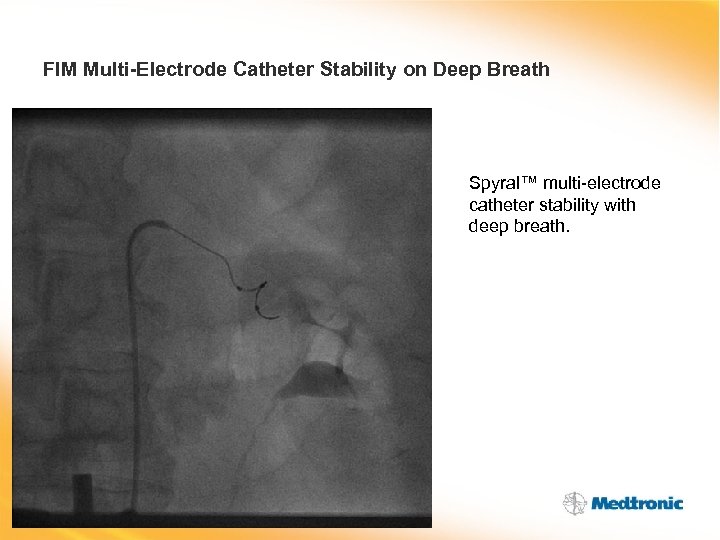

FIM Multi-Electrode Catheter Stability on Deep Breath Spyral™ multi-electrode catheter stability with deep breath.

FIM Multi-Electrode Catheter Stability on Deep Breath Spyral™ multi-electrode catheter stability with deep breath.